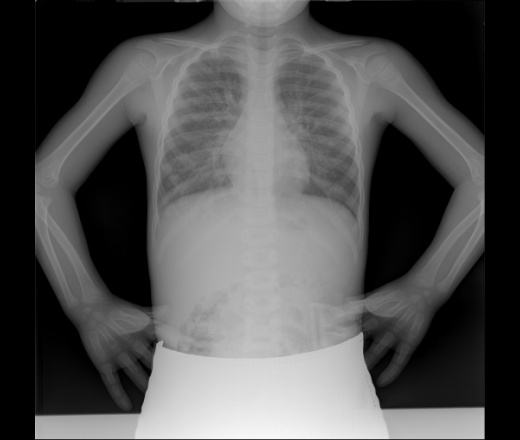

Просто показать. Муковисцидоз

Может кому будет интересно, сам первы1 раз столкнулся. Ребёнок 6лет. Диагноз подтверждён.

Показать должно быть стыдно.  Качество ужасное. Или шторки сломались? Тоже плохо. Нельзя работать на неисправном оборудовании

- проблема в том, что на очень большом количестве исправного современного цифрового оборудования, шторки автоматически задаются на размер плоскопанельного детектора, а их к аппарату придаётся только два и оба большие (типа 35х35), и лаборанты не решаются вручную диафрагмировать, боясь сломать автоматику (и в чем-то я их понимаю)

Присоединяюсь к благодарным пользователям👍 Прогноз? С муковисцедозом обычно долго не живут, но возможны менее тяжелые случаи.